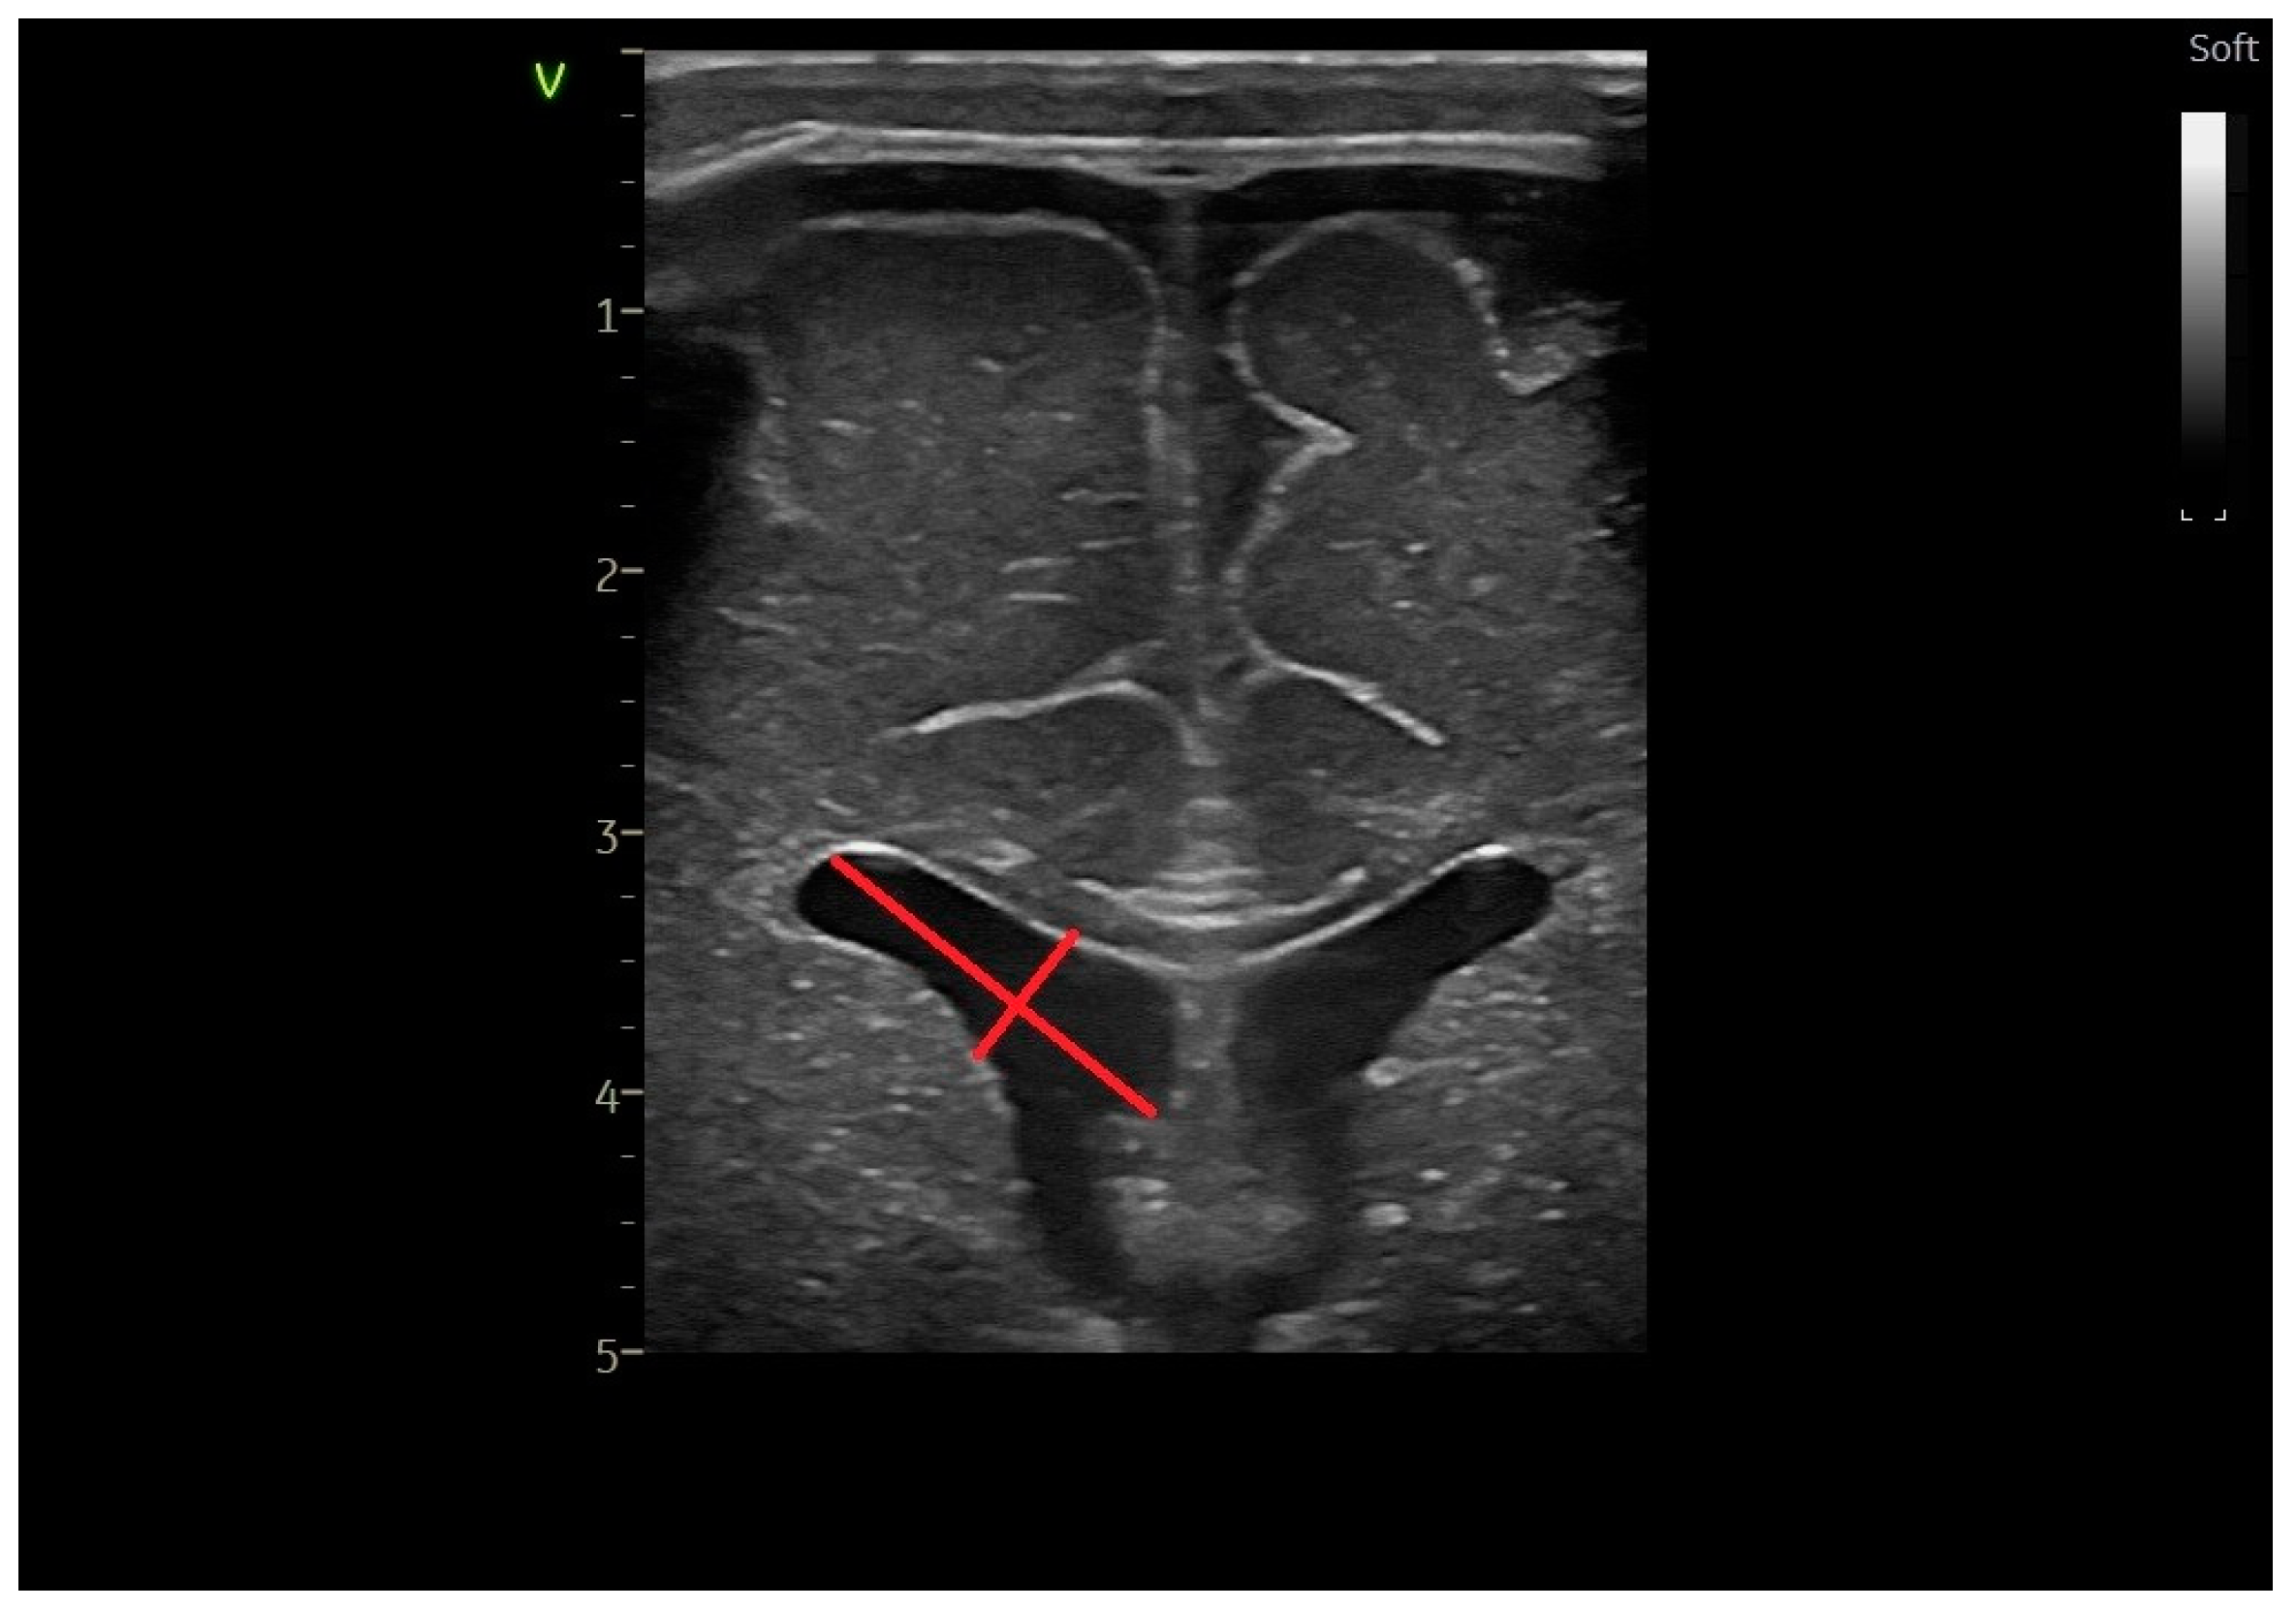

2.2. Head Ultrasound Measurements at TEA